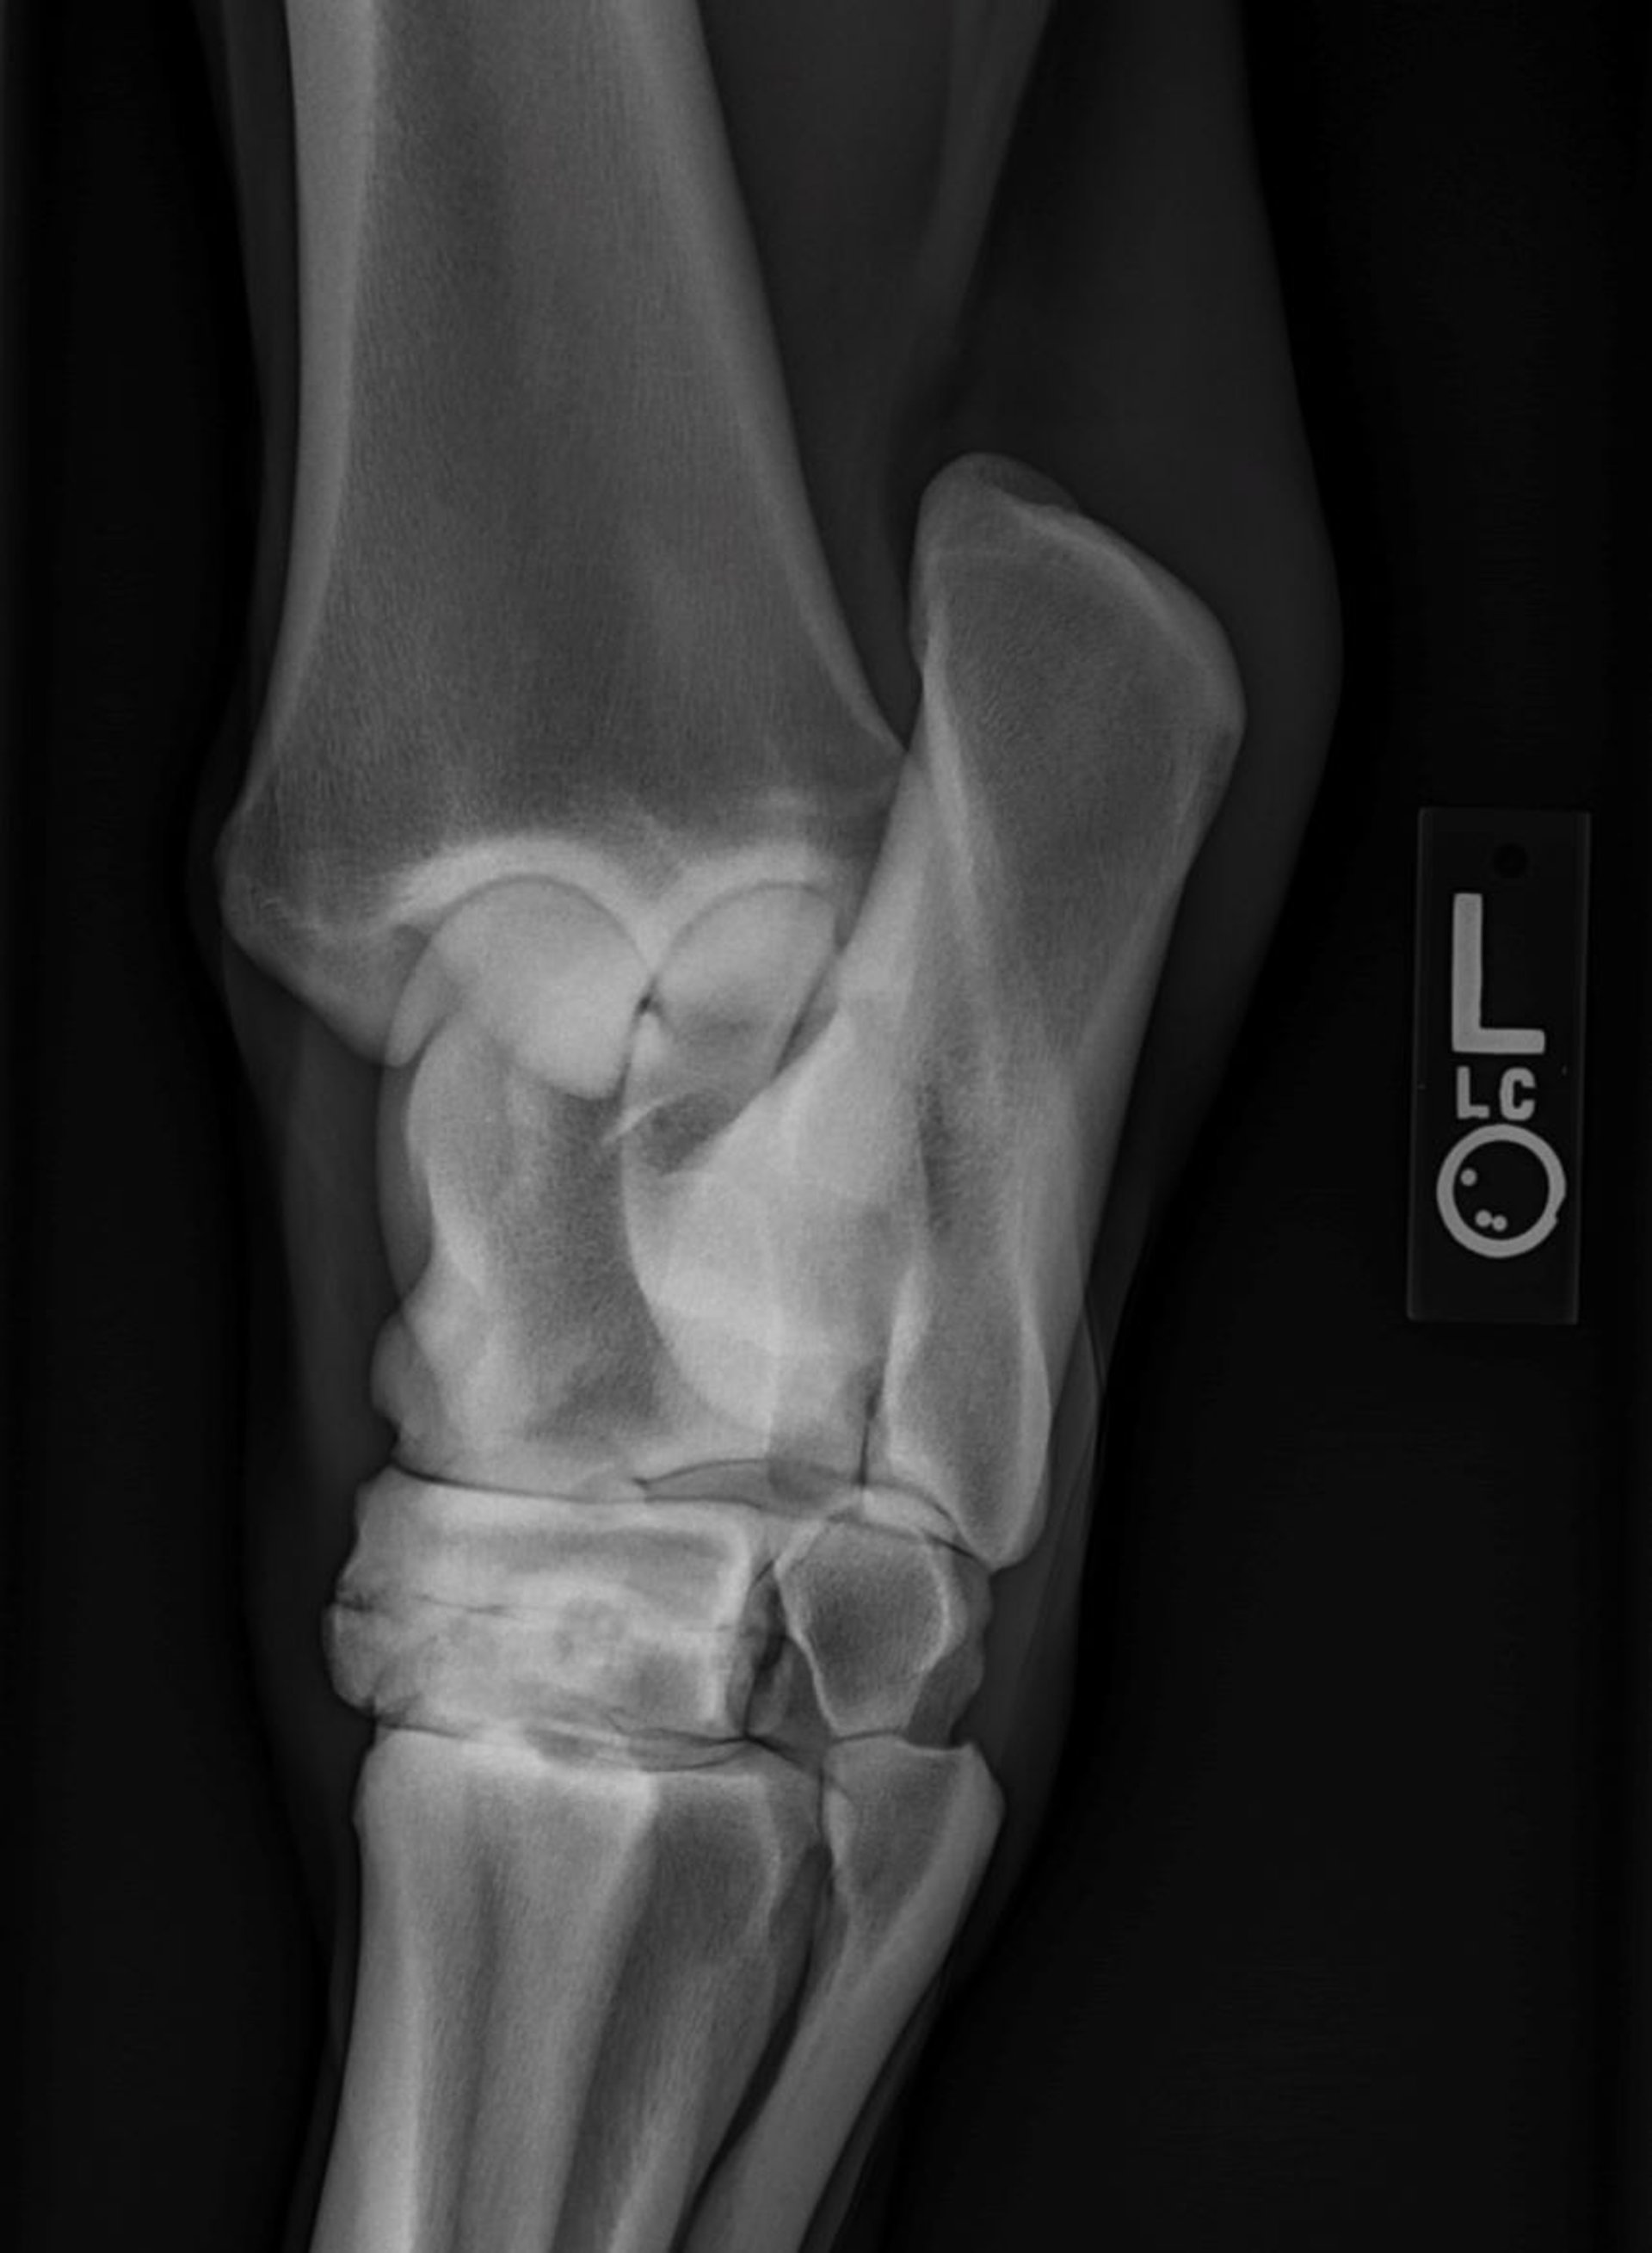

Distal intertarsal osteoarthritis, radiograph, horse

Dorsolateral-plantaromedial radiograph of a horse, showing distal intertarsal joint osteoarthritis. Note the loss of joint space, sclerosis, and osteolysis in the subchondral bone.

Courtesy of Dr. Hilary Rice.